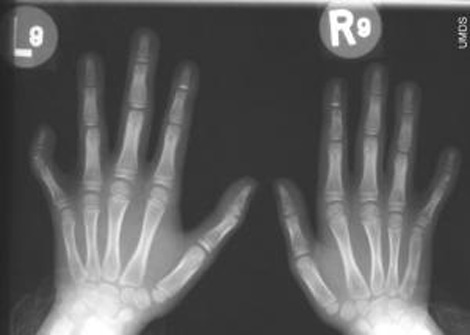

A short 5th metacarpal bone (50%) has been observed in about half of Williams syndrome patients - see picture below; a short 4th metacarpal bone (40%) is also very common (source: I. Borg et al., 2015).

Clinodactyly of the 5th finger (50%) is also seen in about half of William syndrome patients - see picture below; clinodactyly of the 4th finger (10%) may be present as well (source: I. Borg et al., 2015).